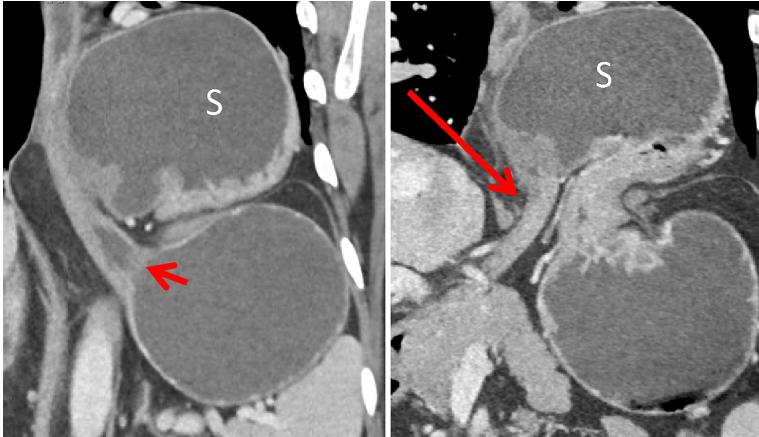

中年女性,因坐骨神经痛使用强的松治疗后出现恶心。冠状位 CT 示胃窦部偏心性增厚及粘膜下水肿,胃体部正常。内镜活检证实为急性胃炎。

中年男性,突发吞咽困难。冠状位 CT 增强静脉期示胃体部位置上移至幽门上方,食管胃连接处位置仍正常。

中年男性,突发恶心呕吐。冠状位 CT 增强门脉期示胃窦部套叠,伴胃内容物潴留。手术证实为胃窦部增生型性息肉所致套叠,此息肉在 CT 上显示不清。